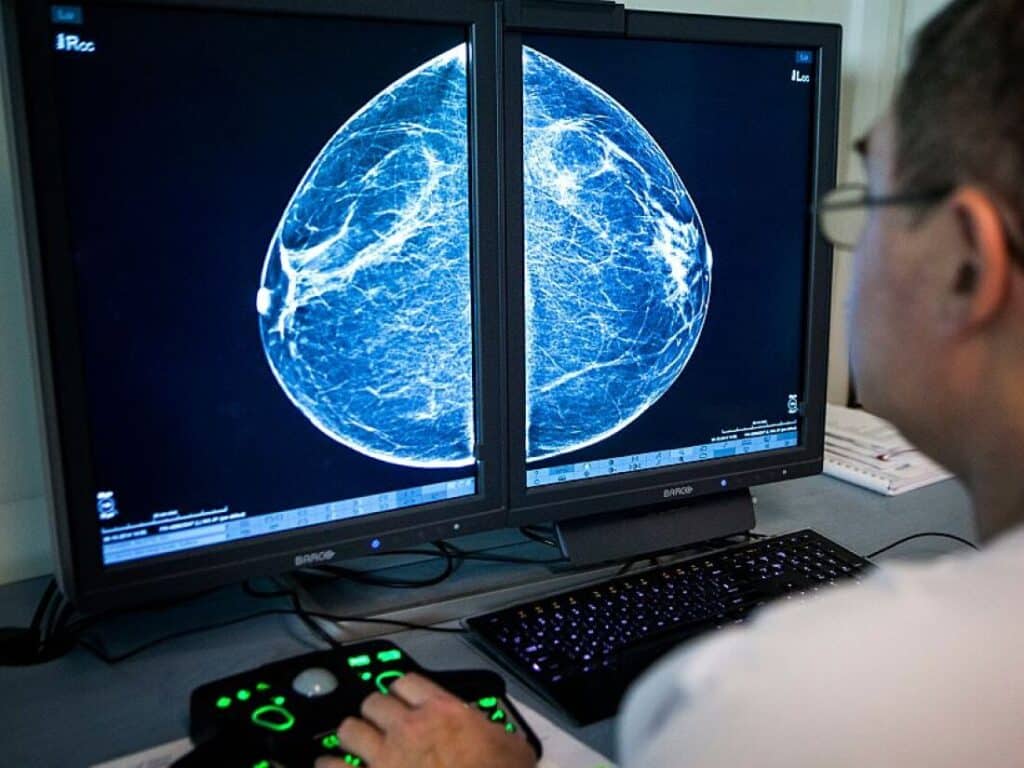

Some clinics will now check your breast scan for arterial calcification, which can be a sign of heart disease risk. But questions remain about the approach.

(Image credit: BSIP/Universal Images Group)